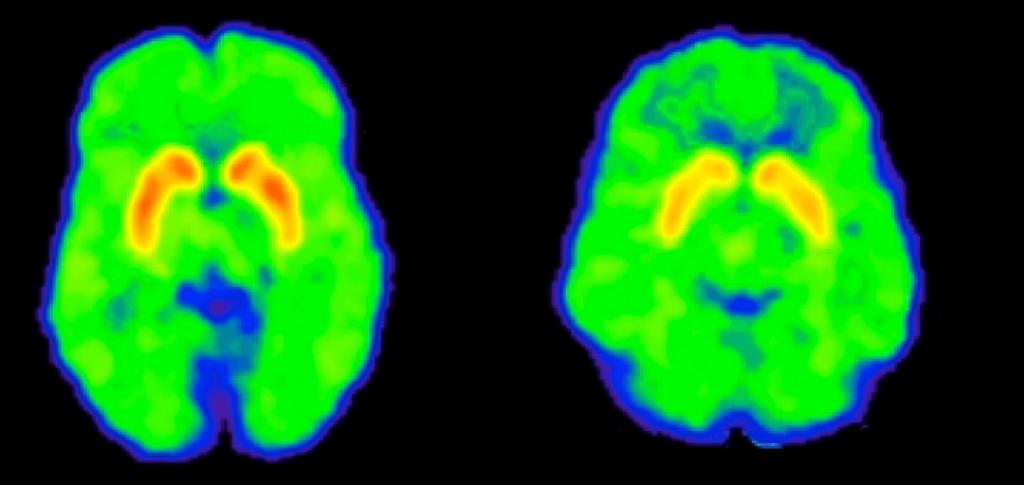

Children born in August in states with a September 1 cutoff for school enrollment are 30% more likely to be diagnosed with

#ADHD. http://ms.spr.ly/6013rhSfS pic.twitter.com/ESDT86zFxf ಧನ್ಯವಾದಗಳು. Twitter ಇದನ್ನು ನಿಮ್ಮ ಕಾಲರೇಖೆಯನ್ನು ಉತ್ತಮಗೊಳಿಸಲು ಬಳಸುತ್ತದೆ. ರದ್ದುಗೊಳಿಸುರದ್ದುಗೊಳಿಸು